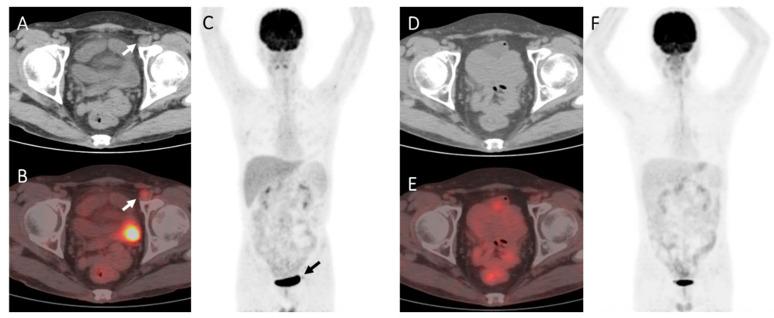

A total of 185 patients (235 post-transplantation PET/CT scans) were enrolled in our present study. Compared with those with true-positive PET results, patients with false-positive PET results exhibited a better prognosis. For the autologous SCT group, false-positive cases were more commonly seen when FDG-avid foci appeared outside the sites of the original disease ( = 0.004), and the integrated CT imaging showed negative results ( = 0.000). In multivariate logistic regression analysis, integrated CT results were the only significant factor. For the allogeneic SCT group, false-positive cases were significantly more commonly seen when DS = 4 ( = 0.046), FDG-avid foci appeared outside the sites of the original disease ( = 0.022), and the integrated CT imaging showed negative results ( = 0.001). In a multivariate logistic regression analysis, whether FDG-avid foci were in the sites of the original disease and integrated CT results were both significant factors.

False-positive FDG uptake in post-transplantation PET was not uncommon. Several variables could provide an important reference to differentiate false-positive from true-positive post-SCT PET results for lymphoma involvement.